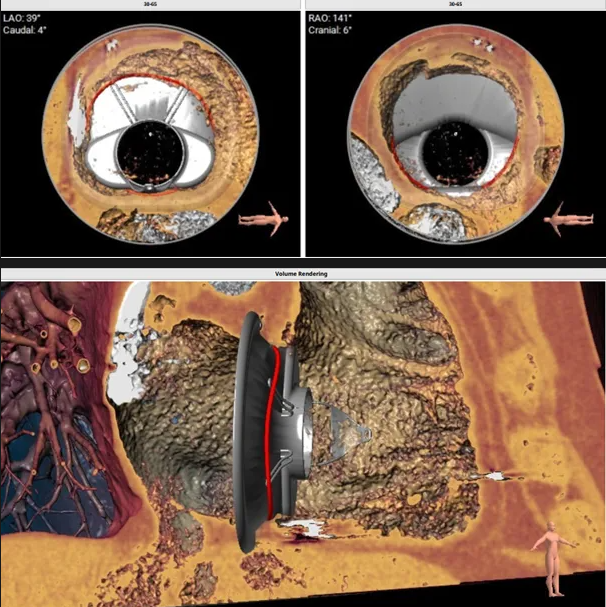

三尖瓣環切線位夾角 85°

瓣膜植入模擬